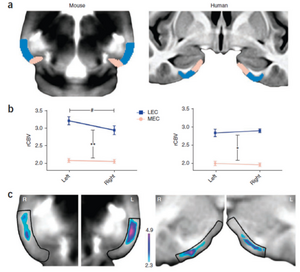

- 4.41 Molecular Drivers and Cortical Spread of Lateral Entorhinal Cortex Dysfunction in Preclinical Alzheimer’s Disease

- 4.42 Retrosigmoid Implantation of an Active Bone Conduction Stimulator in a Patient with Chronic Otitis Media